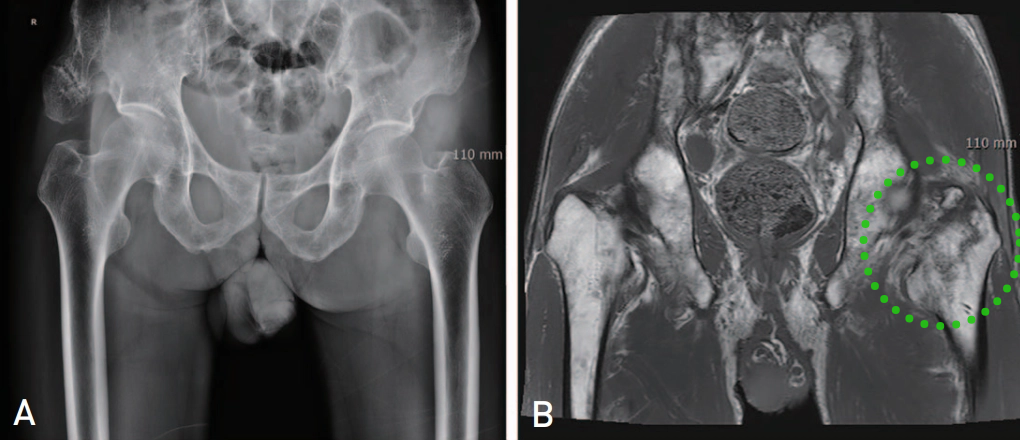

▲ 图示87岁女性患者,摔伤致右髋部疼痛。A:X线检查提示右髋孤立性大转子骨折;B:骨扫描提示孤立性大转子骨折;C:MR提示右股骨粗隆间骨折。

7例同时行CT和磁共振检查的患者中,3例CT提示为孤立性大转子骨折,但磁共振显示所有7例患者的骨折均延伸至转子间内侧1/2皮质,其中4例接受了手术治疗。